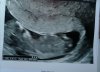

Melduję się bo badaniach, dzidzia ma 5,30 cm, robi fikołki i wg usg dziś 12+0 także kilka dni starsza 😁😁😁 wszystko w porządku i trzymam kciuki za resztę dzisiejszych wizytujących!!! W poczekalni myślałam że serce wypluje 😱 ale już po wszystkim, teraz prenatalne 🙄🙄 miłego dnia wszystkim ❤️😘

W jaki sposób mialas badania? Zastanawia mnie to bo miałam ciągle dowcipnie i dziecko było widać od tyłu (plecy) i zastanawiam się czy jak będę miała przez brzuch to będzie widać dzidzie z boku.. Widzę że też u ciebie mały pęcherzyk a dzidzia duża.. Już się balam że tylko ja tak mam..